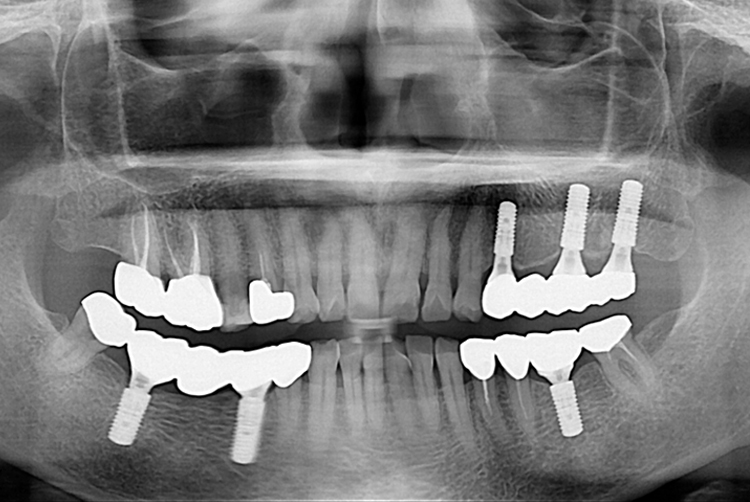

439c1bbeb51925d110ef969c2b2848bd.jpg

치료전 : 2018-07-24